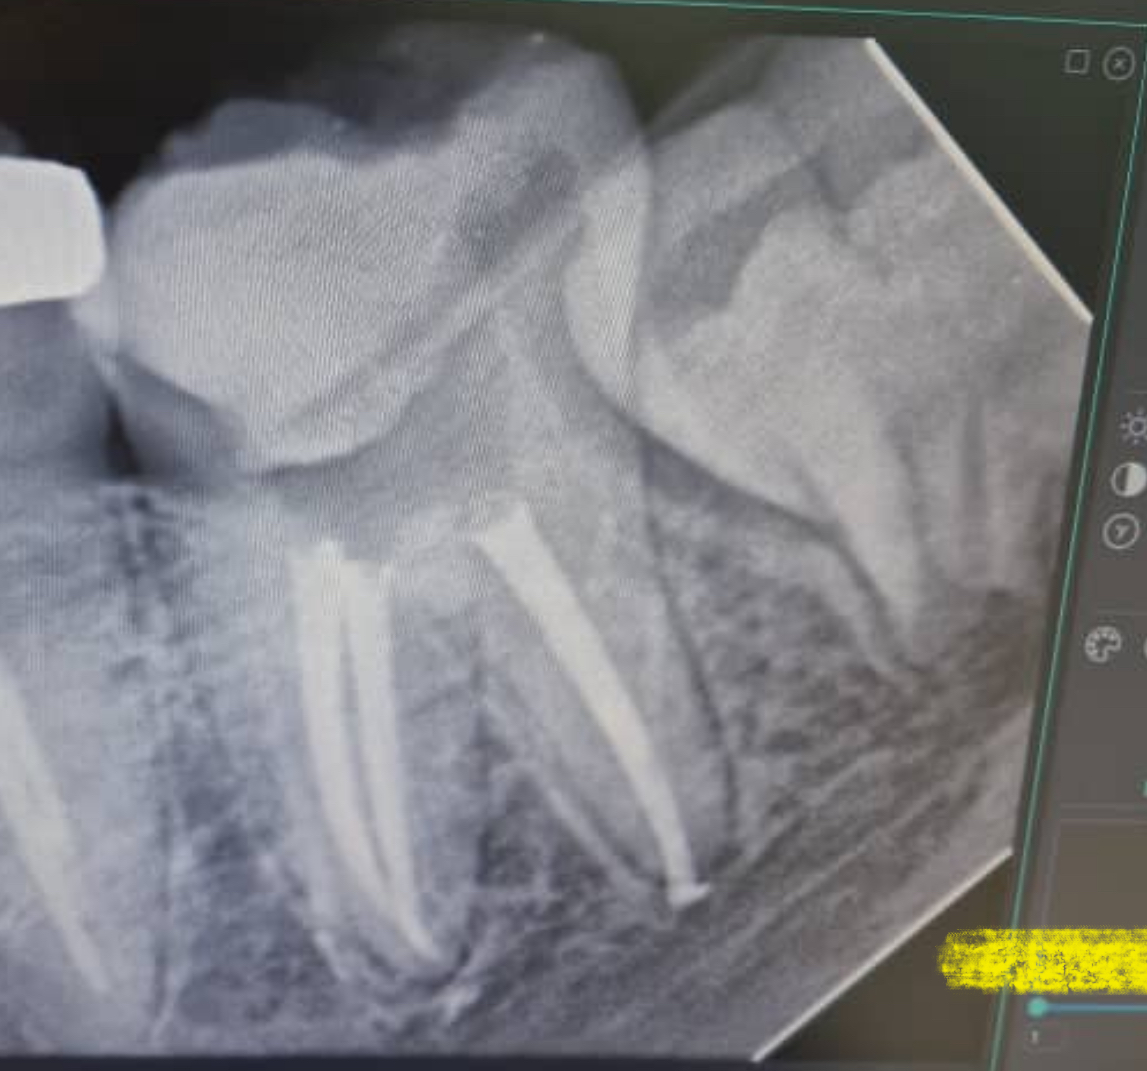

توجه کنید که بیشتر این مراحل بدون دیدن همهٔ طول کانال با صرف اتکا به دانش، تجربه، دستگاههای پیشرفته و رادیوگرافی صورت میگیرد. ازاینجهت ریشهدرمانی کاری پیچیده و حساس تلقی میشود.

درد بعد از درمان ریشه نشان دهنده کیفیت درمان نیست و ممکن است یک درمان ریشه بی کیفیت هیچ گونه دردی نداشته باشد ولی یک درمان ریشه عالی درد شدیدی داشته باشد . در واقع جهت مشخص شدن کیفیت درمان ریشه بهتر است که رادیوگرافی دندان تهیه شود گرچه موفقیت طولانی مدت درمان ریشه را نمی توان صد در صد با گرافی تعیین نمود .